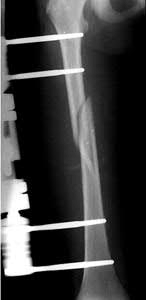

Figure A demonstrates a displaced subtrochanteric femur fracture with an intact lesser trochanter. The pull of iliopsoas on the lesser trochanter as well as the intact external rotators and gluteal musculature results in the the proximal fragment being in a flexed and externally rotated or abducted position (the most common post operative deformity). Reduction manuevers must be biologically friendly but also counteract the flexion/abduction moment. Lundy's review article discusses evaluation and treatment of subtrochanteric fractures. The review article details the various implants often used which include 95 degrees plates, femoral reconstruction nails, or trochanteric femoral nails with interlocking options. Lundy's article discourages the use of the 135 degree screw and side plate combo due to high failure rates in these fracture patterns. Bedi et al also review treatment of these fractures and discuss common

problems of malunion, nonunion, and implant failure. The article reviews reduction techniques that are soft tissue friendly, as well as the use of appropriate implants in these fracture types.